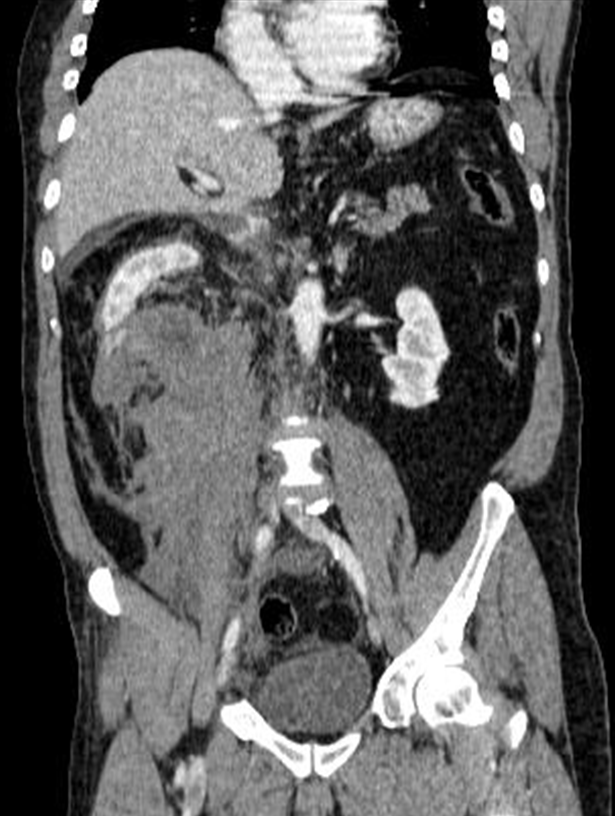

En este caso, se indica reconstrucción multiplanar del TC realizado, en la que se ve más claramente la laceración del polo renal inferior derecho y la expansión del hematoma perirrenal (riñón derecho).